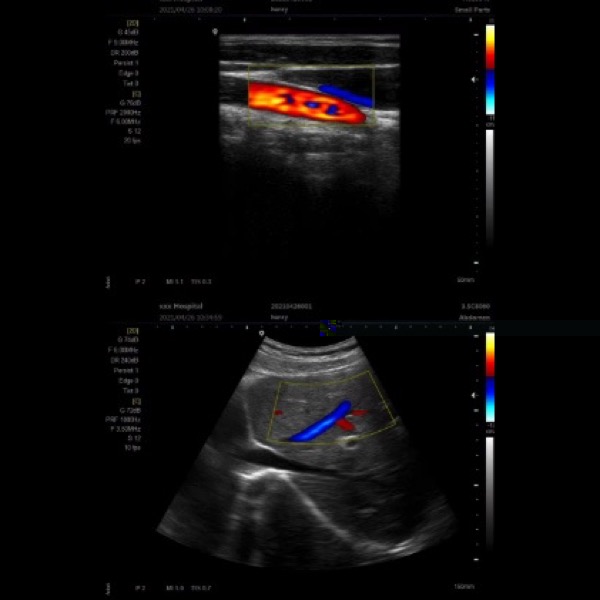

Modes d image :B,B/B,4B,B+M,CFM,B+CFM,PDI,B+PDI,PW

Applications cliniques : Abdomen, cardiologie, obstétrique, gynécologie, urologie, pédiatrie, petits organes,cardiaque.